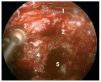

Caso clínico: Varón de 42 años de edad con paresia del VI par craneal derecho y estudios de imagen mediante resonancia magnética y tomografía computarizada craneales sugestivos de displasia fibrosa esfenoclival. Se lleva a cabo un abordaje endonasal expandido transpterigoideo completamente endoscópico, obteniéndose una amplia descompresión de las estructuras vasculonerviosas de la base del cráneo. Durante el procedimiento se utiliza neuronavegación y el canal vidiano como referencia anatómica fundamental de la carótida en su segmento lacerum.

Conclusiones: El abordaje endonasal expandido transperigoideo para el tratamiento de la DF basicraneal es un método seguro y eficaz gracias a la guía que el canal del nervio vidiano proporciona para localizar el segmento lacerum de la arteria carótida.

Case report: A 42-year-old male with right sixth cranial nerve palsy. Cranial MRI and CT showed a central skull base lesion with diagnostic suspicion of FD. Patient underwent a full endoscopic transpterygoid EEA, achieving a wide skull base neurovascular decompression. Neuronavigation and the vidian canal landmark resulted mandatory during intraoperative procedure.

Conclusion: Transpterygoid EEA for treatment of FD of the skull base is a safe and effective procedure, thanks to the guide that the vidian canal provides in finding the lacerum segment of the carotid artery.